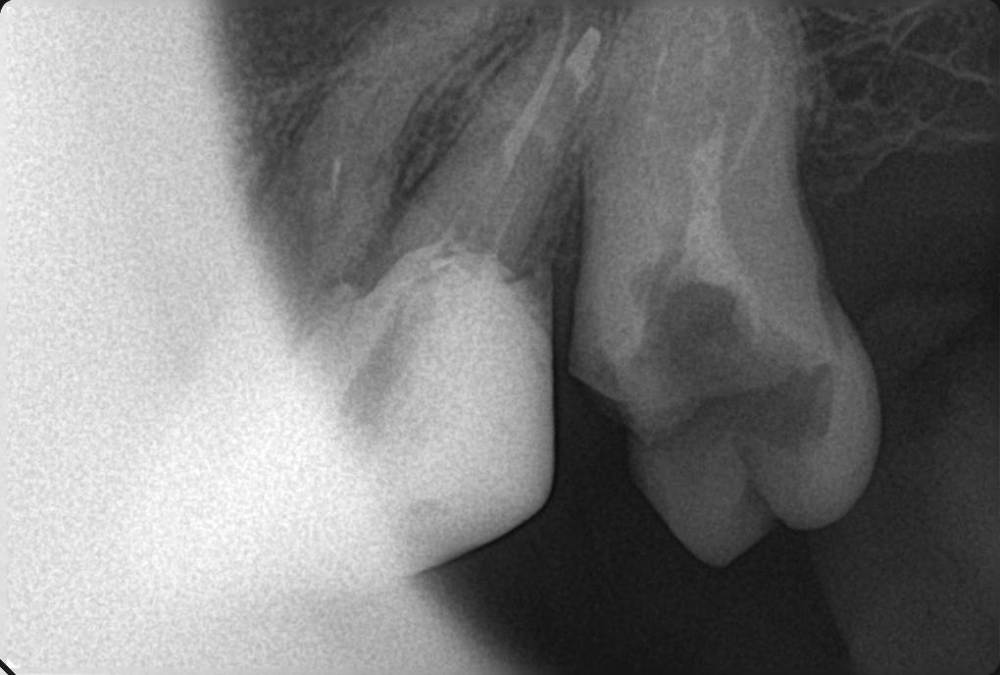

GENRY Опубликовано 6 сентября, 2021 Поделиться Опубликовано 6 сентября, 2021 Здравствуйте! Как лучше восстановить ( пусть частично) 28 зуб? Удаление не желательно т.к. с имплантацией связываться не хочу (синус лифтинг.. возраст 75 лет...) ,а опор для ортопедических конструкций нет. Кроме того боюсь, что в процессе удаления будет разрушена пломба 27 _го. Оптимизма добавляет история 27 го На орто 2012г показан 27 до его восстановления и до вмешательства в 28 зуб с добавлением в него пломбы в 2012г . Канал 28_го (небный ?) был уже запломбирован кем то раньше, скорее всего резорцин-формалиновой пастой) Доктор в 27 - м обнаружил на снимках 3 канала, наполовину прошел небный и полностью прошел дистально- щечный канал с наполнением их горячей гуттаперчей . Поскольку устье 3_го канала обнаружено не было, восстановил 27 зуб 2_мя стекловолоконными штифтами с использованием Build-It . Дистальную стенку сделал, кажется на основе пасты СПЕКТРУМ . К дальнейшей судьбе 27_го доктор отнесся скептически ( не более 2_х лет!), но похоже сработал надежно, пошел уже 10_й год, а 27 все стоит. Но 10 мес. назад выпала пломба 28 _го и он принял вид показанный на снимке. Не беспокоит. Хотелось бы повторить историю с 27_м, т.е. восстановить 28 по типу 27_го .... думаю мне хватит 5_7 лет... Регулировать нагрузки на этой стороне челюсти я научился. Сделал КТ сегмента 27_28 (В Пикассо, Vatech, просмотрщик EZ3D2009 plus ) но не смог найти ( сейчас живу в Феодосии ) терапевта работающего с этой программой. Кто то вообще не использует никакие КТ (но при этом берется за восстановление штифтом без перелечивания каналов) , кто то готов к перелечиванию, но полагается только на свои мануальные навыки, игнорируя КТ или формально глянув на пару проекций. На последней консультации добился 4-х снимков из КТ, но в общем то случайных и скорее всего не показательных.. Выкладываю скриншоты... Понял, что надо выходить за пределы городка и расширять собственное (к сожалению) понимание возможных вариантов лечения и их последствий. Вопросы по 28: 1. Если хотя бы один канал запломбирован (видимый на снимке) то это автоматически означает вскрытие камеры , а значит вскрытие и убитость содержимого (нервов, сосудов) всех остальных каналов , поскольку их устья на дне камеры? (Да, Нет, Другое) 2. Если Да, то нормально ли было пломбировать 28, не найдя и не залечив (с пломбировкой) другие каналы одновременно с небным (я имею ввиду сейчас самую раннюю пломбировку, до представленного орто) 3. Поскольку пломбировки всех каналов (сколько их ?) точно не было, то за эти 10-15 (?) лет (уже сейчас зуб стоит открытым почти год (ковид, консультации..)) должен развится пульпит, периодонтит... ? Или не обязательно? Ничего не болело, никаких выделений не было 4. Есть ли признаки какой либо хроники, воспалений в тканях на снимках? 5. Если ткани зуба и около него в порядке, то может не обязательно перелечивать все каналы, чтобы не ослаблять зуб? А только те, в которые будут вставлены штифты? Вкладка, похоже исключается т.к. феррул не замкнут на стыке с 27 зубом. 6. Есть ли какие либо оценки минимального количества требуемых штифтов ? 7 . Поскольку за 4 консультации я так и не получил ответов и снимков срезов (по КТ )показывающих количество и топологию корней и каналов, то придется добывать эту информацию самому. Буду благодарен за ссылки на материалы показывающих как это делается т.е. в каких из 3 проекций, при каком положении осей и.т.п. Я нашел только хороший ролик Ервандяна А.Г., но мне недостаточно, не хватает знания топологии зубов. Спасибо за внимание. Ссылка на комментарий

GENRY Опубликовано 8 сентября, 2021 Автор Поделиться Опубликовано 8 сентября, 2021 12 часов назад, dentikl сказал: покажите плз фото нижних и верхних передних зубов.Можно телефоном.Верхние-чтобы увидеть режущий край (если он сохранен) Представленная раньше орто сделана в 2012г. Произошли изменения: 11,21,22 - живые с коронками; 12 - коронка на вкладке; 24 - был треснут, эндопролечен (фото прилагается), восстановлен; 13,23 - живые, но сильно стерты, особенно у десны . Займусь ими после разборки с 28 (и 18). они стоят открытые, На 17 одета металлическая коронка. 18 лишился пломбы 2 мес. назад. На след. неделе еду на его лечение. Снимок 17,18 перед лечением в 2013 _ прилагаю Ссылка на комментарий